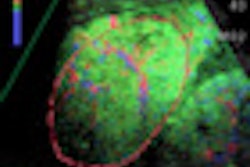

Back at the WFUMB congress, there was plenty of discussion about hepatic imaging. Firstly, evidence was presented about how contrast-enhanced ultrasound can help to characterize liver disease. Click here for our article.

Secondly, speakers described how elastography can permit rapid assessment of liver fibrosis that seems free of adverse events, is comfortable for the patient and sonographer, and has a mean duration of around five minutes. Click here to learn more.